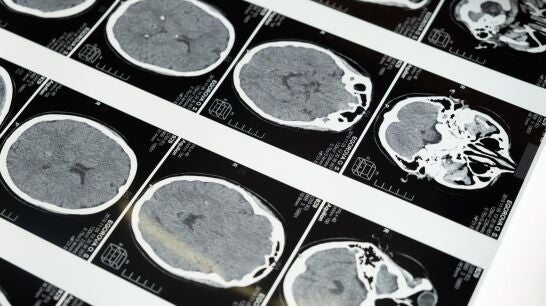

En España se diagnostican cada año 5000 nuevos casos. El cáncer cerebral es un término bajo el que se aglutinan más de 120 tipos de tumores del sistema nervioso. Desde la Sociedad Española de Neurología explican las claves.

Cada año se diagnostican en España más de 5000 nuevos casos de cáncer o tumor cerebral, un término bajo el que se aglutinan más de 120 tipos de tumores del sistema nervioso.

"En los últimos años se ha observado un incremento en el número de casos anuales debido, principalmente, a la mejora de las técnicas de imagen -lo que ha permitido perfeccionar su diagnóstico-, y al progresivo envejecimiento de la población", explican desde la Sociedad Española de Neurología (SEN), con motivo del Día Internacional de los Tumores Cerebrales (8 de junio).